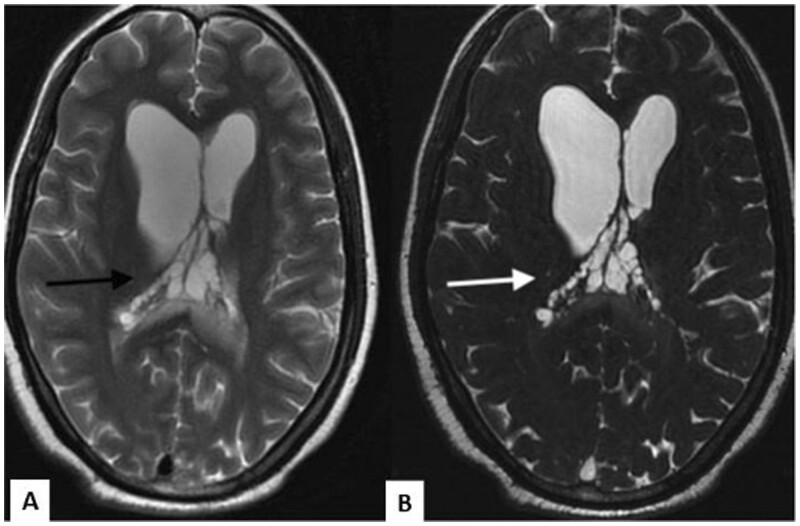

神经囊尾蚴病(NCC)是世界某些地区常见的中枢神经系统寄生虫病。总状型神经囊虫病与常见的实质型神经囊虫病截然不同。它经常浸润基底蝶窦和西尔维窝。影像学检查在诊断中起着至关重要的作用;然而,由于其信号强度与脑脊液相似,而且在大多数病例中没有增强,因此常规 MRI 序列的影像学诊断往往比较困难。在此,我们介绍了五例消旋体 NCC 病例,以强调重 T2 加权序列(快速成像稳态采集)序列在诊断这种疾病中的重要性。

Neurocysticercosis (NCC) is a common parasitic condition of the central nervous system in certain parts of the world. The racemose variety of NCC is distinct from the commonly seen parenchymal form. It frequently infiltrates the basal cisterns and Sylvian fissures. Imaging plays a vital role in the diagnosis; however, as their signal intensity is similar to cerebrospinal fluid and due to the absence of enhancement in most cases, imaging diagnosis is often difficult on the conventional MRI sequences. Here, we present five cases of racemose NCC to emphasize the importance of a heavily T2-weighted sequence (Fast Imaging Employing Steady-state Acquisition) sequence in the diagnosing this entity.